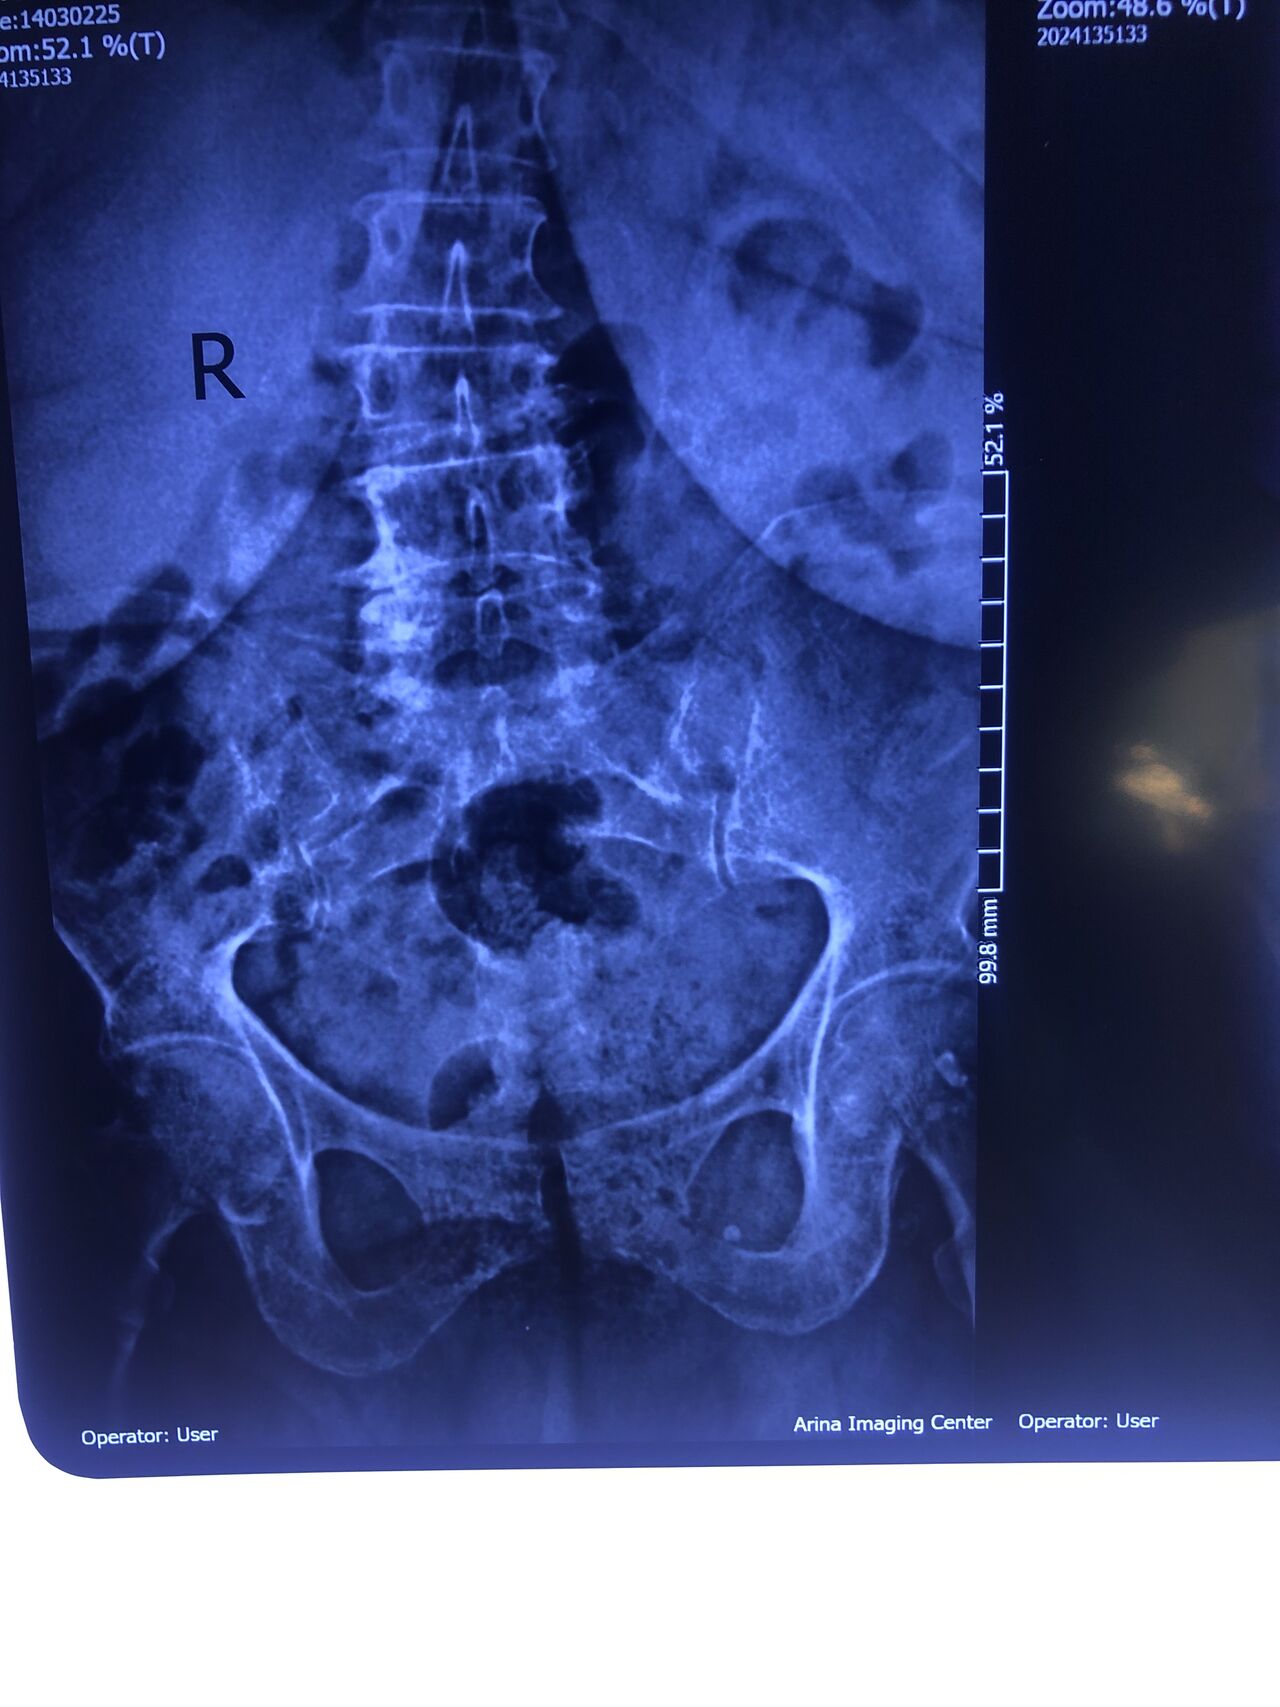

Case 24

86 years old male patient was referred to me by a neurologist one week ago for evaluation and choosing proper plane of management ( he trusts me in handling patients properly)

Patient has had severe LBP for the last 2 weeks

Had history of prostate cancer surgery 20 years ago

What are your DDxs and POM?